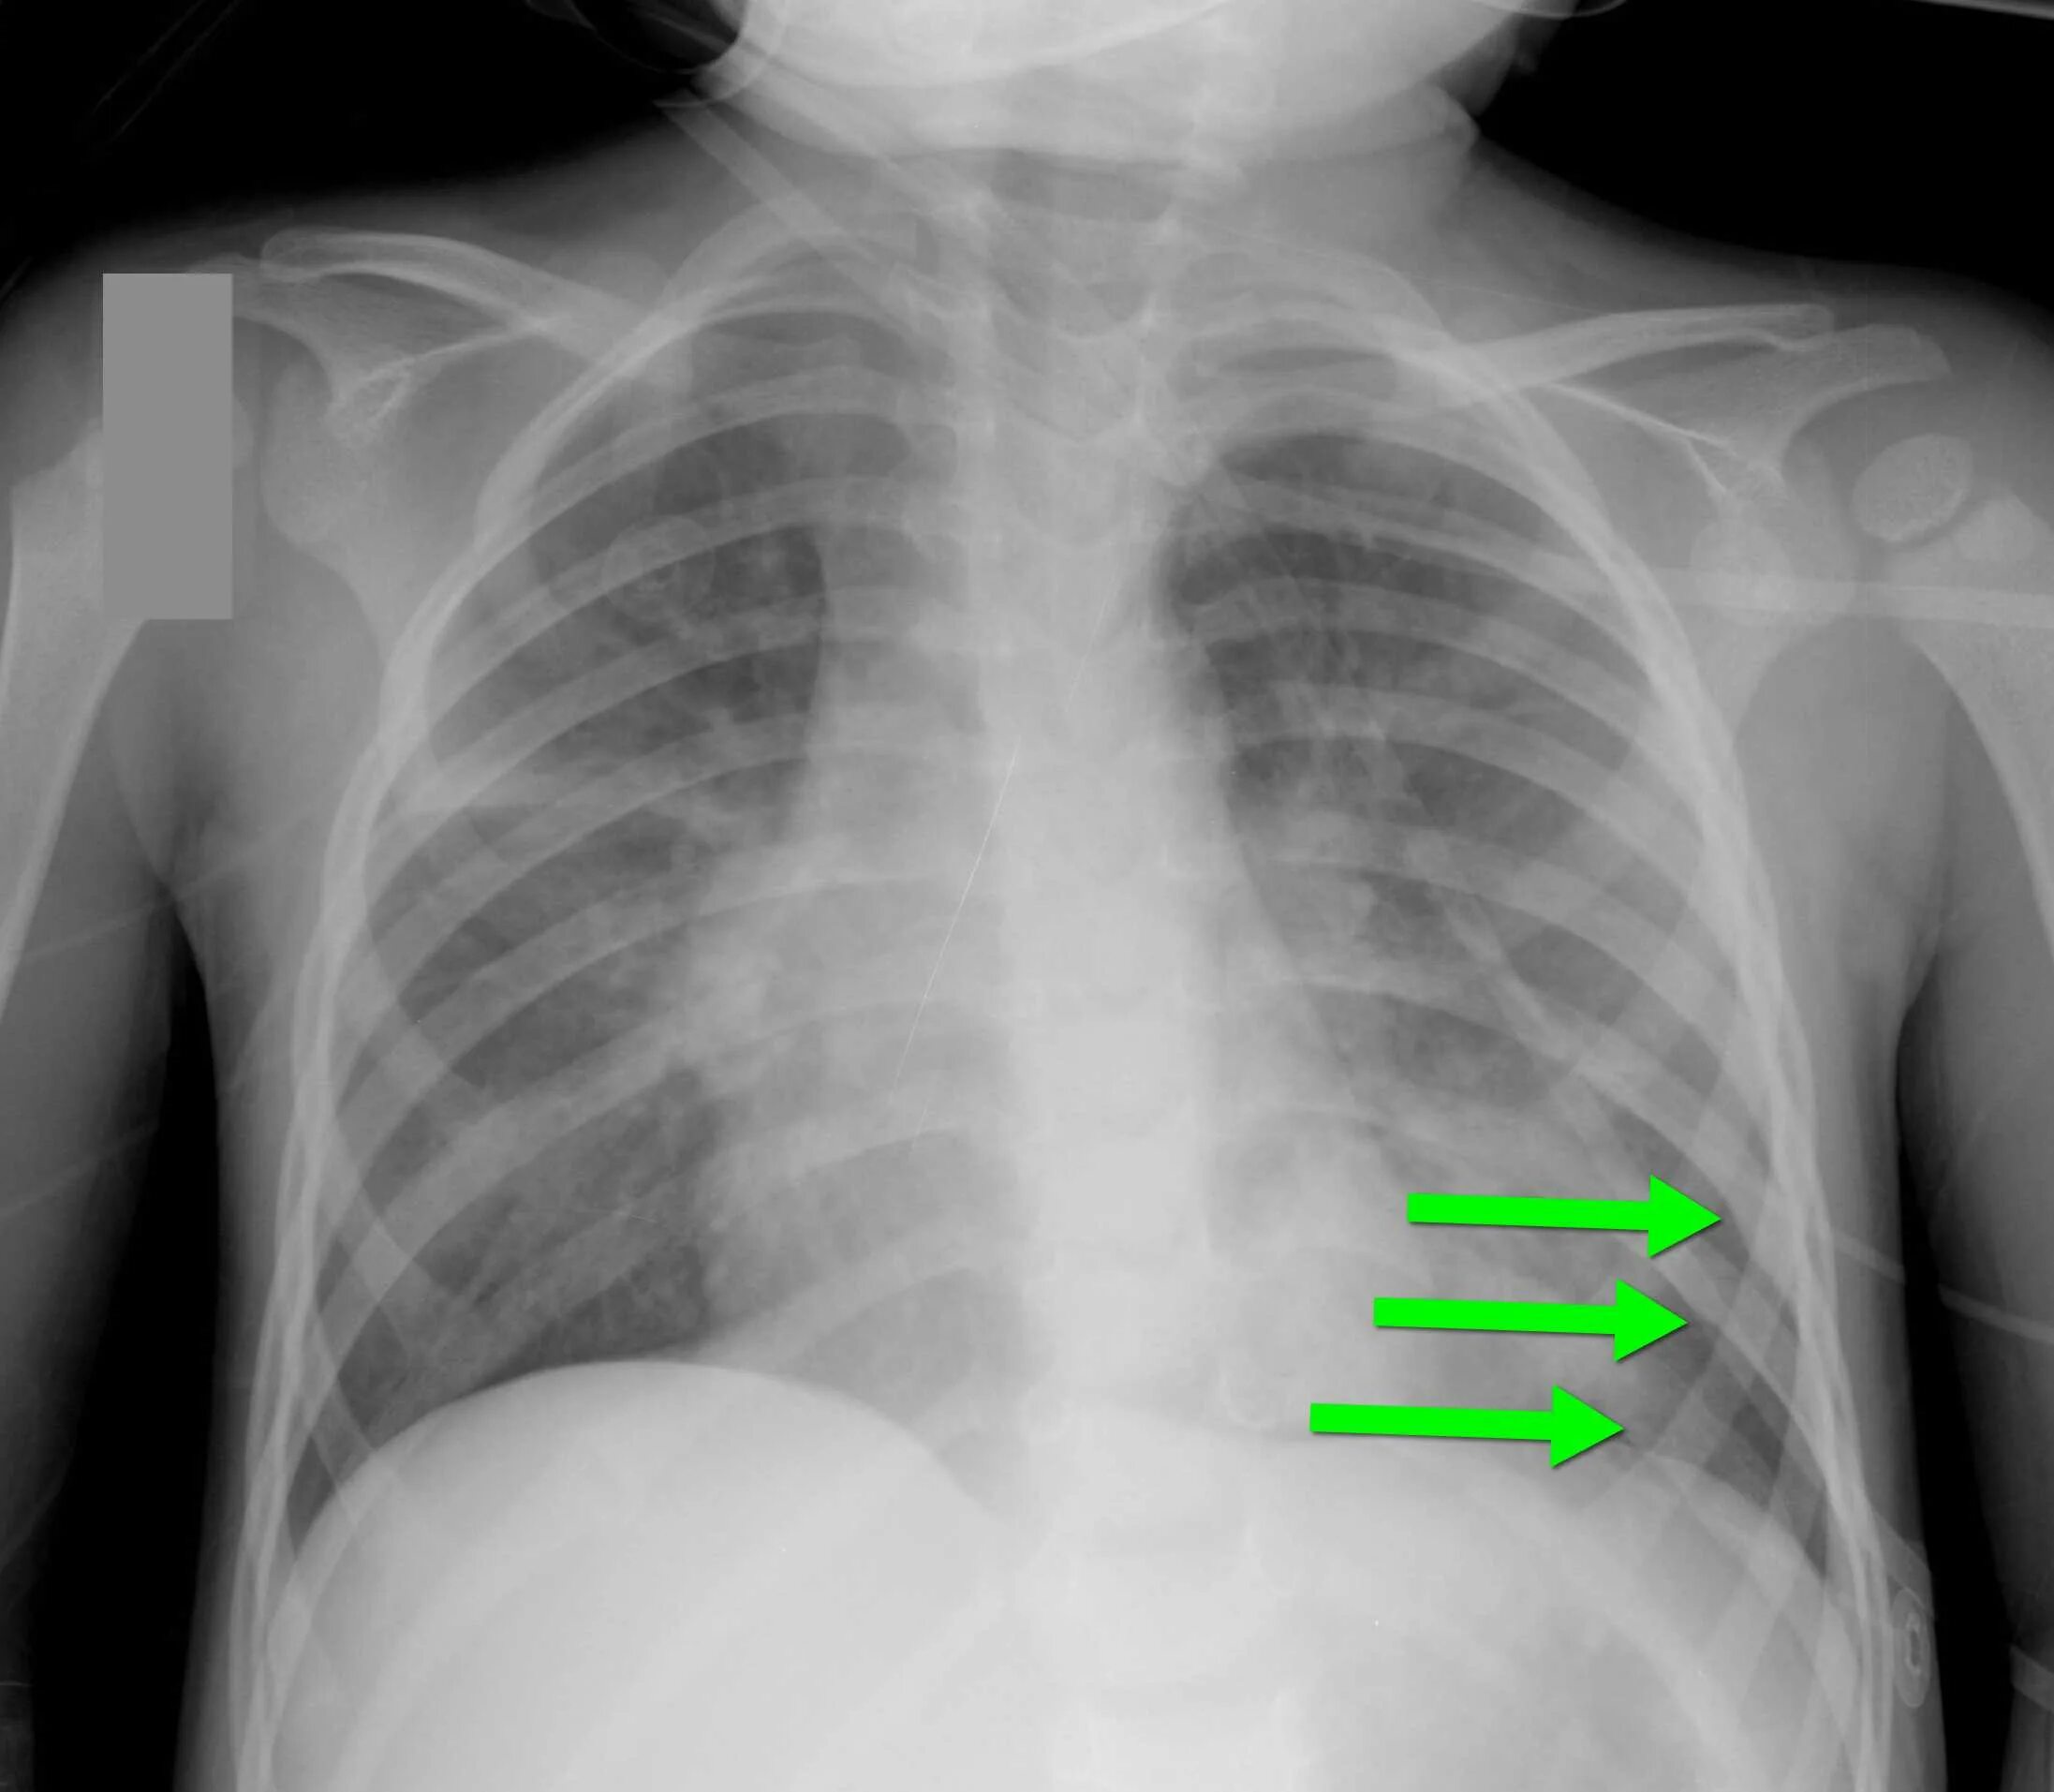

Сколько срастается ребро при переломе